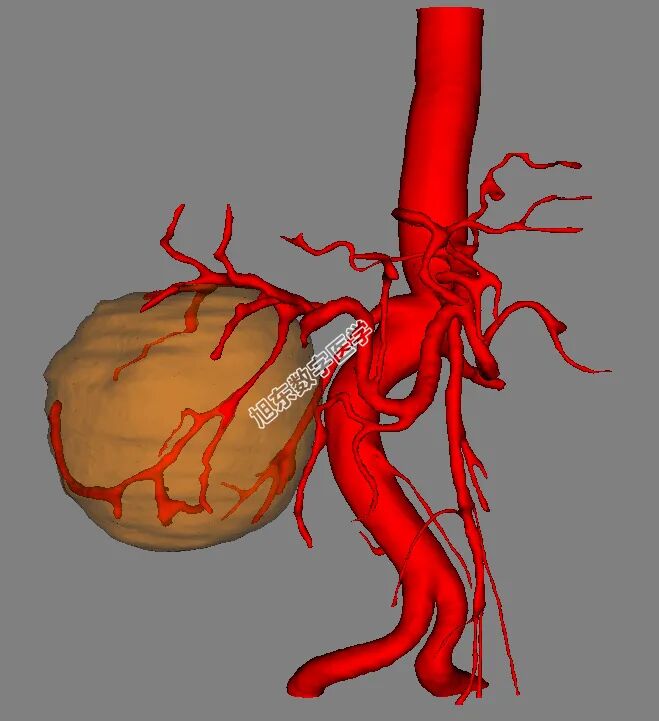

占位与动脉血管解剖关系

占位与门静血管解剖关系

占位与肝静脉解剖关系

3D可视化入路规划